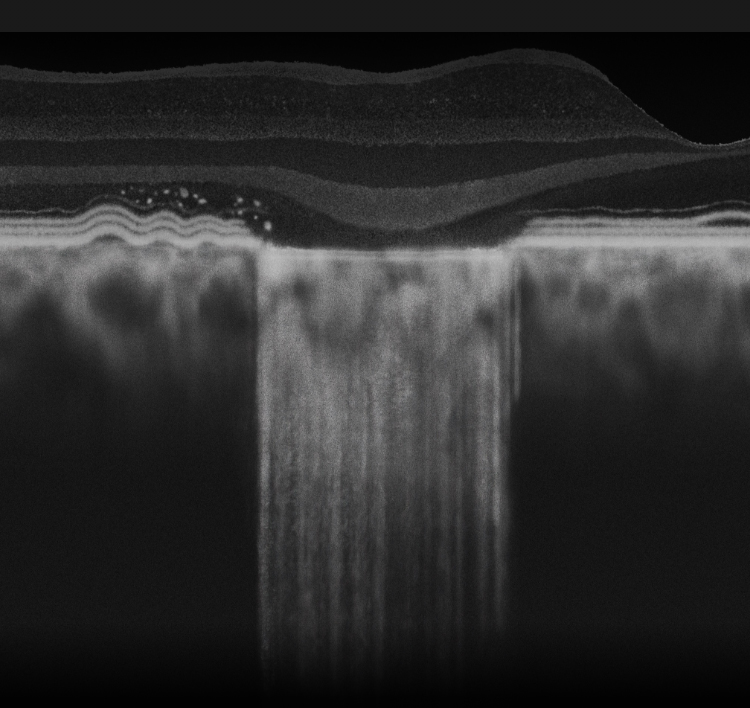

SEE THE SIGNS OF GEOGRAPHIC ATROPHY (GA)

It is critical to recognize GA and refer patients in a timely manner, as disease progression is relentless and irreversible1,4-8

Learn how to recognize GA

OCT=optical coherence tomography.